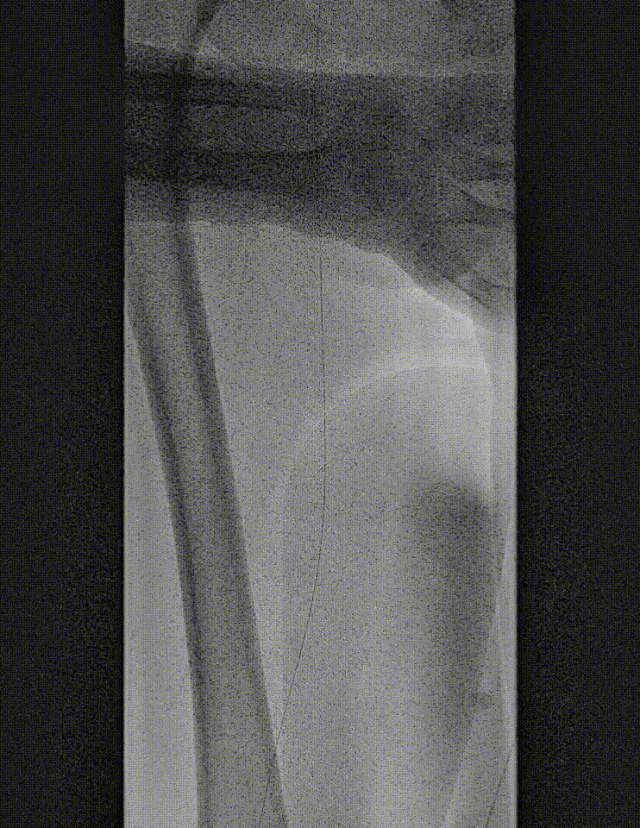

图:DA 造影+通过病变

图:造影及通过病变

图:OA 基线造影

图:LA 基线造影